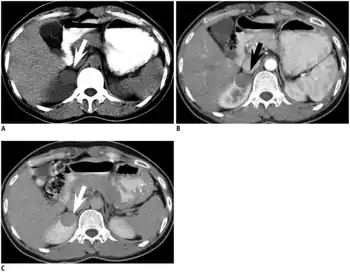

Symptoms and signs

Metanephric adenoma is diagnosed histologically. The tumours can be located at upper pole, lower pole and mid-hilar region of the kidney; they are well circumscribed but unencapsulated, tan pink, with possible cystic and hemorrhagic foci. They show a uniform architecture of closely packed acinar or tubular structures of mature and bland appearance with scanty interposed stroma.[3][4][5][6][7] Cells are small with dark staining nuclei and inconspicuous nucleoli. Blastema is absent whereas calcospherites may be present. Glomeruloid figures are a striking finding, reminiscent of early fetal metenephric tissue. The lumen of the acini may contain otherwise epithelial infoldings or fibrillary material but it is quite often empty. Mitoses are conspicuously absent.[3][4][5][6][7] In the series reported by Jones et al. tumour cells were reactive for Leu7 in 3 cases of 5, to vimentine in 4 of 6, to cytocheratin in 2 of 6, to epithelial membrane antigen in 1 of 6 cases and muscle specific antigen in 1 of 6.[5] Olgac et al. found that intense and diffuse immunoreactivity for alpha-methylacyl-CoA racemase (AMACR) is useful in differentiating renal cell carcinoma from MA but a panel including AMACR, CK7 and CD57 is better in this differential diagnosis.[8] Differential diagnosis may be quite difficult indeed as exemplified by the three malignancies initially diagnosed as MA that later metastasized, in the report by Pins et al.[9]